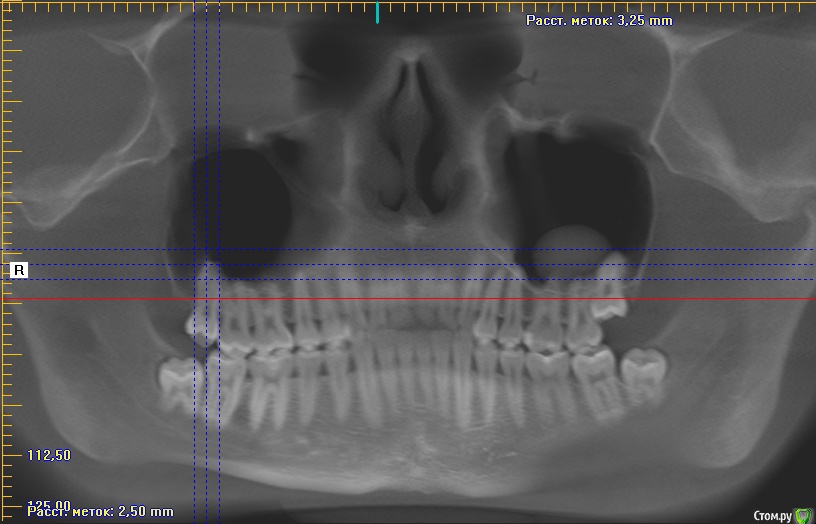

Добрый день коллеги,плановое удаление 8 зубов ,верхние в гайморовой ,что за образование в левой жалоб нет никаких.Что вы делаете при вскрытии пазухи?